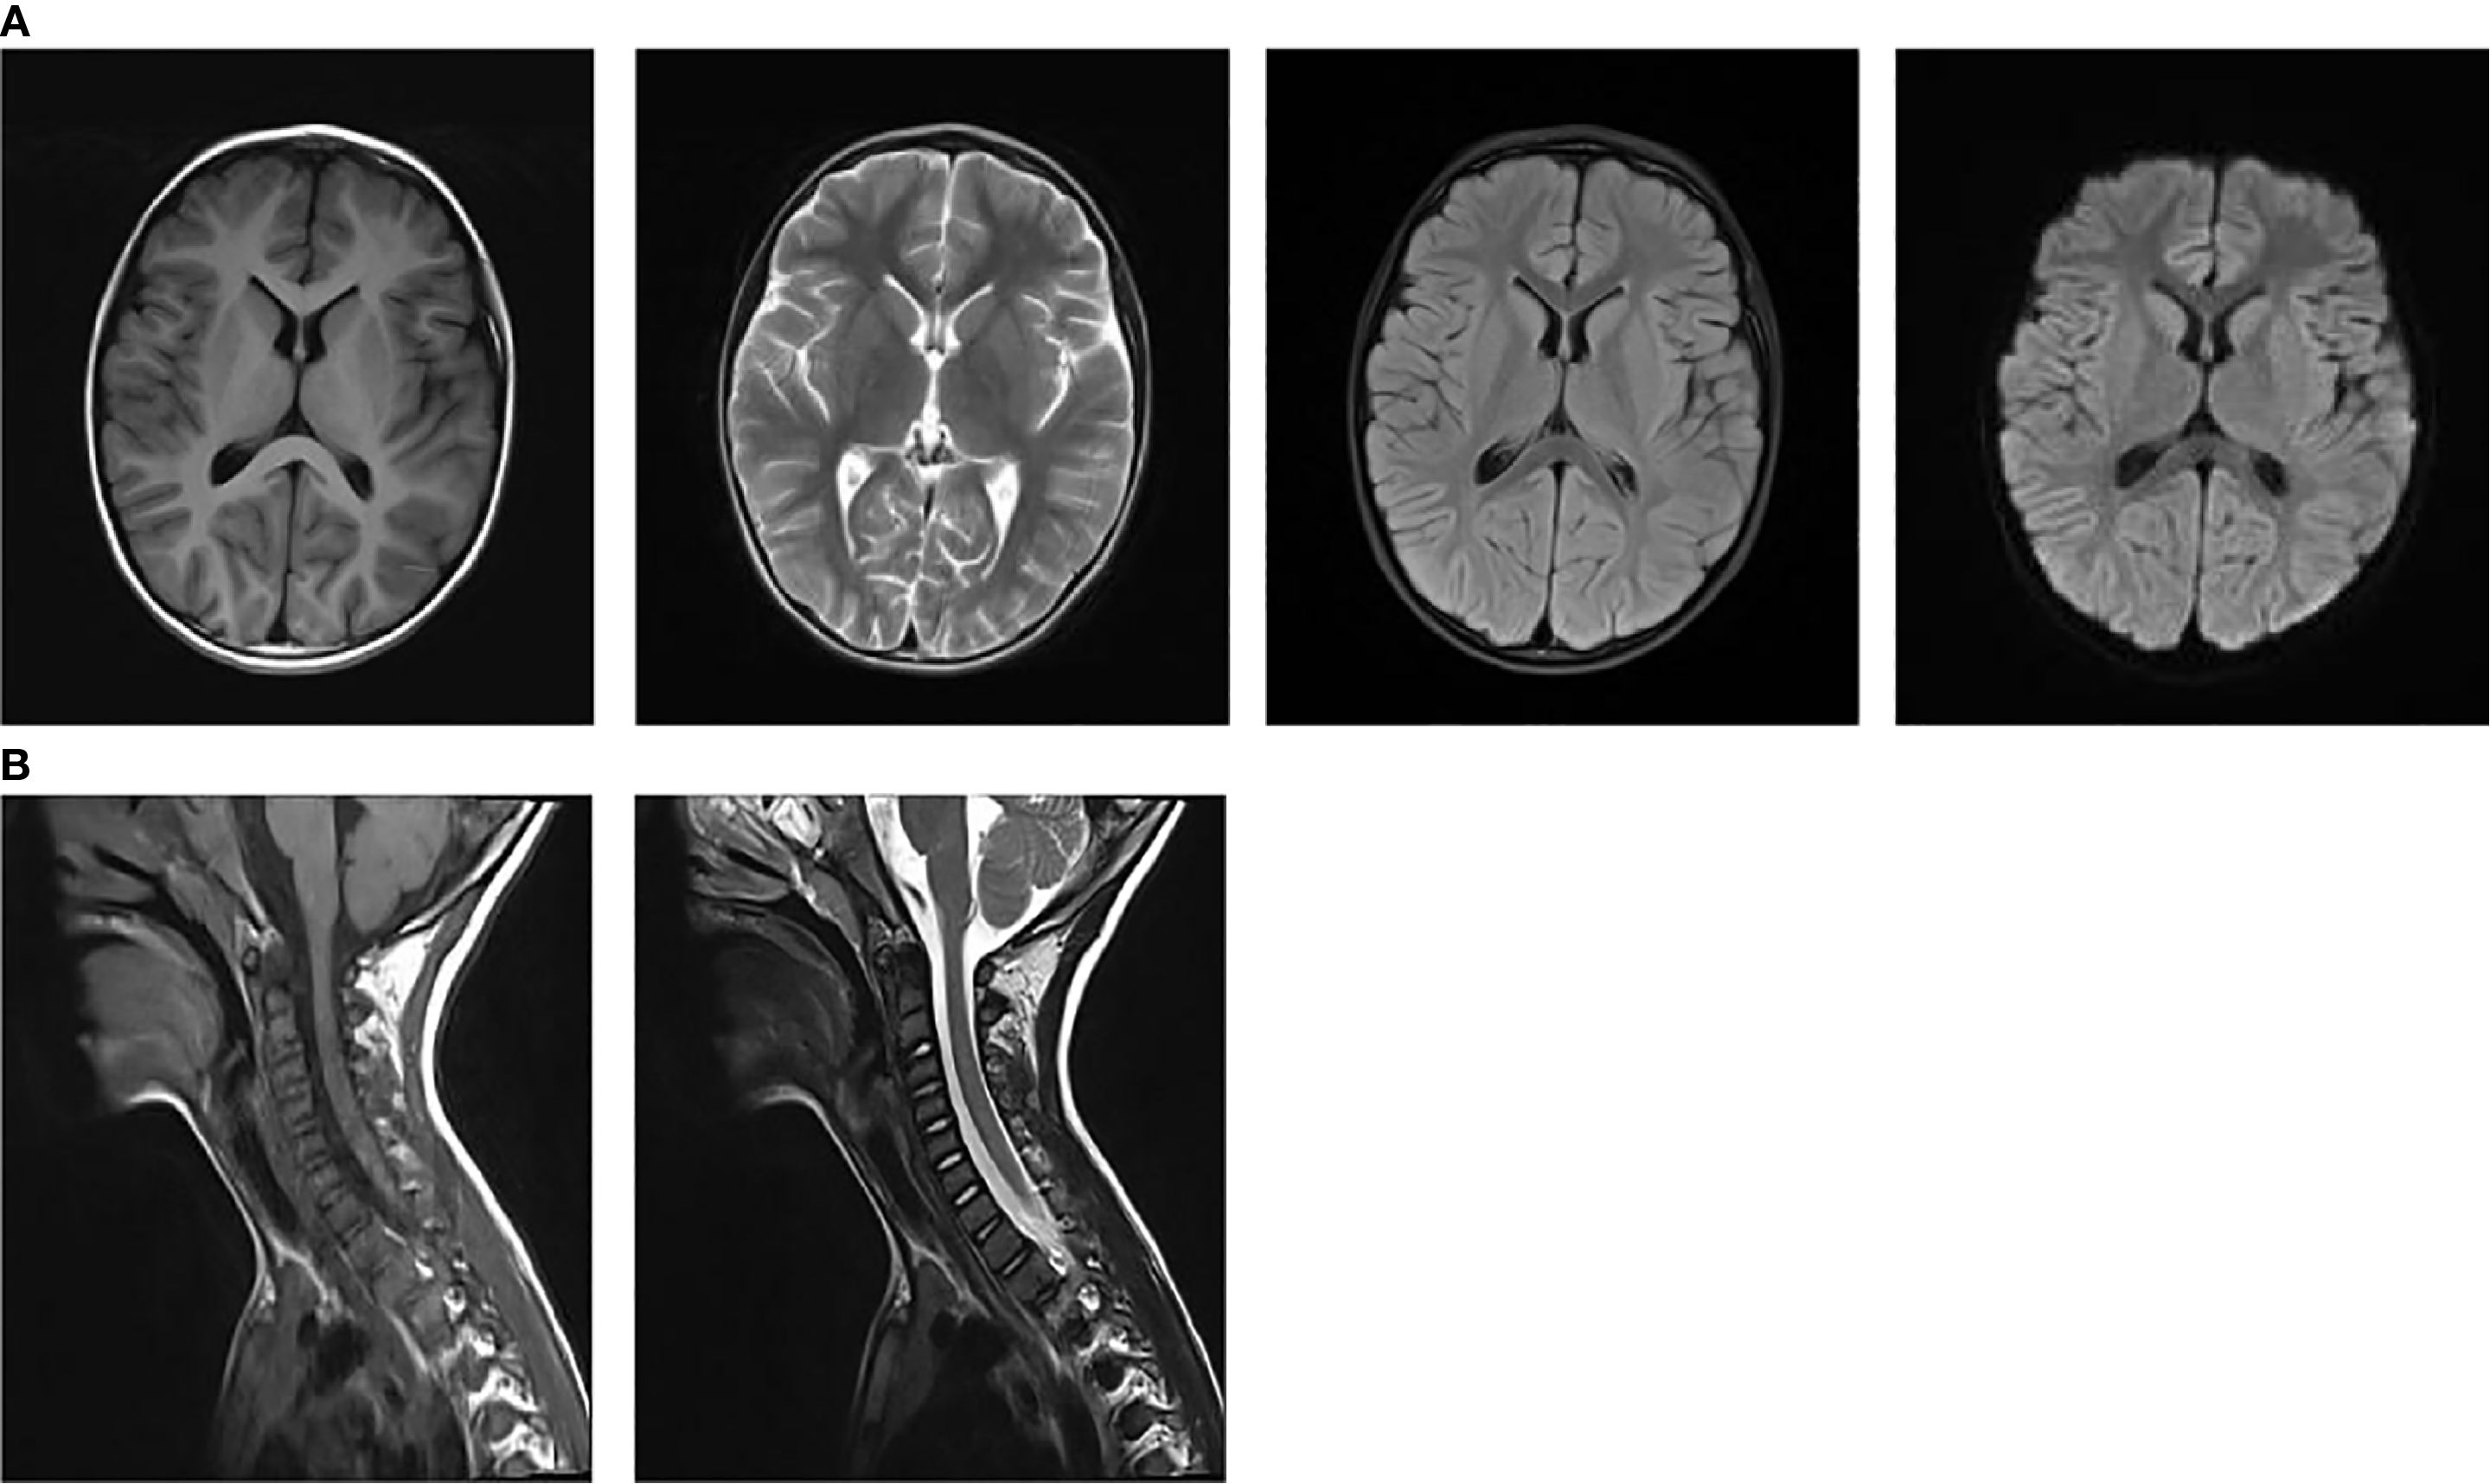

On admission, nasopharyngeal swab test was positive for H1N1. Routine laboratory exams showed mild neutrophilic leukocytosis and raised inflammatory markers (PCT 0.25 ng/ml, n.v. <0.05; interleukin 6 109.05 pg/ml, n.v. <7.1; interleukin 10 49.1pg/ml, n.v. <10.6). Chest radiography revealed increased and disorganized bilateral lung markings. Routine and biochemical cerebrospinal fluid (CSF) analysis were normal. CSF microbiological analyses were negative. Diagnostic work-up for malignancy with abdominal and testicular ultrasonography was unremarkable. Antinuclear antibody (ANA) and anti-extractable nuclear antigen antibody (ENA) testing yielded negative results. Thyroid function and thyroid ultrasonography showed no abnormalities.1.5 T magnetic resonance imaging (MRI) of the brain and cervical spinal cord were unremarkable at 1 week after symptoms onset (Figures 1A, B). Electroencephalogram (EEG) with polygraphy excluded a cortical origin of myoclonus. Needle EMG showed continuous motor unit activity (CMUA) and co-activation of agonist and antagonist muscles with normal-appearing motor unit potentials (MUPs), particularly in the lower extremities (Figure 2A). R-CMAPs were recorded by stimulating the median, tibial, and common peroneal nerves for approximately 20–50 milliseconds (Figure 2B).